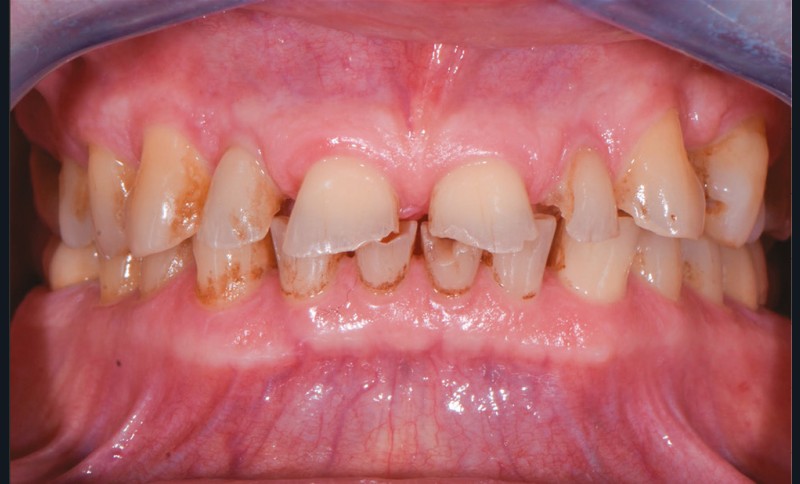

Un patient âgé de 69 ans se présente en consultation pour des problèmes d’ordre fonctionnel et un sourire dégradé. Selon l’adage de Peter Dawson, « l’esthétique et la fonction vont main dans la main », ce cas clinique illustre une situation instable et dysfonctionnelle qui ne sera résolue qu’avec une réhabilitation de la fonction et de l’esthétique (fig. 1 et 2).

Avant tout acte clinique, une étude approfondie est indispensable, nécessitant des données biologiques, occlusales, fonctionnelles et esthétiques. Un examen clinique approfondi et des examens complémentaires (radiologiques, électromyographiques, etc.) permettent de poser un diagnostic et d’envisager une planification thérapeutique (simulation, séquence, évaluation d’un pronostic).